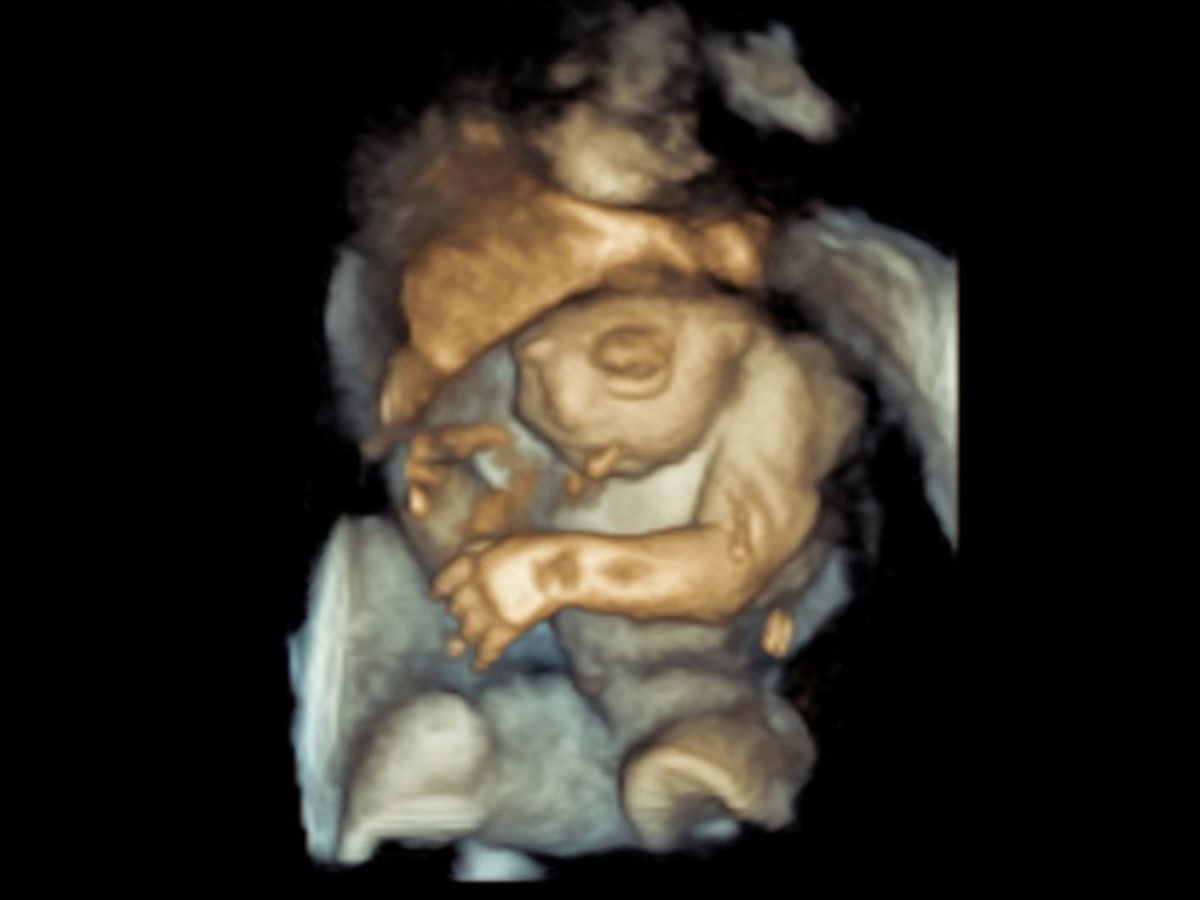

Our unborn baby Cecelia Little Lott has exencephaly, which is an incredibly rare fatal Neural Tube Defect. The Reader's Digest version is that she has a big beautiful brain but is missing her skull vault, the top of her head. Doctors call her condition "incompatible with life." But nobody told her that. She is happily kicking away in my womb as I type this.

Like her name sake, Cecelia loves music. She also loves all things sugary and kicks up a storm whenever she hears her daddy's voice reading stories to us. Her middle name is Little because Jeremy has always called her “Little Lott” since the day we first learned we were pregnant.